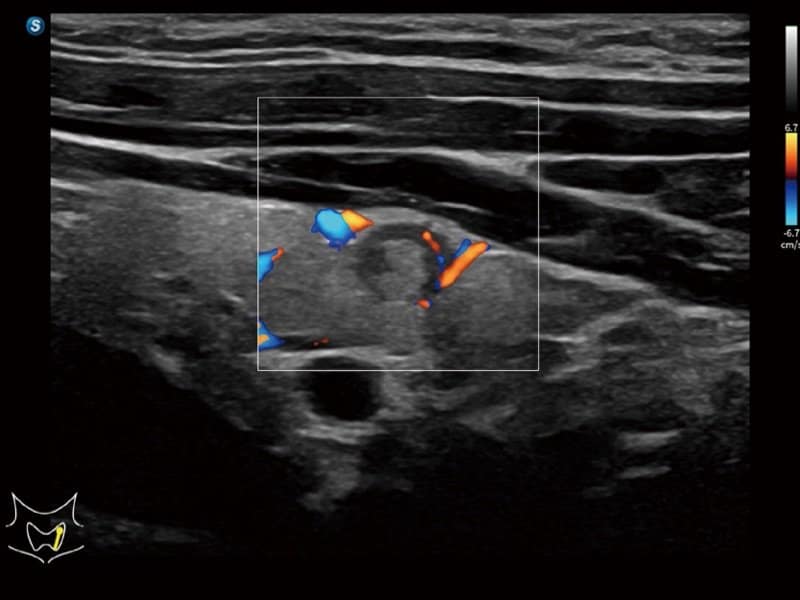

Klinische Bilder

- Kardiologie: Automatische Identifizierung von Herzstrukturen via S-CV (TDI/Messung), Stress-Echokardiographie und MQA zur Bewegungsanalyse.